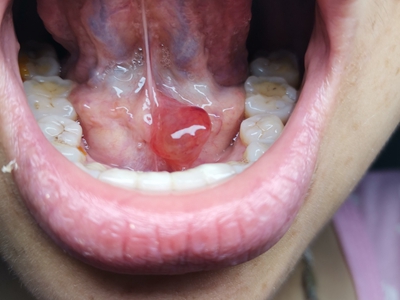

舌下腺囊肿舌底下长了个蚕豆大小的疙瘩图

舌下腺囊肿出现在舌系带一侧,表现为凸出于黏膜表面的疙瘩,如蚕豆大小,质地较软,有异物感,局部自发破溃,流蛋清样液体,常反复出现。